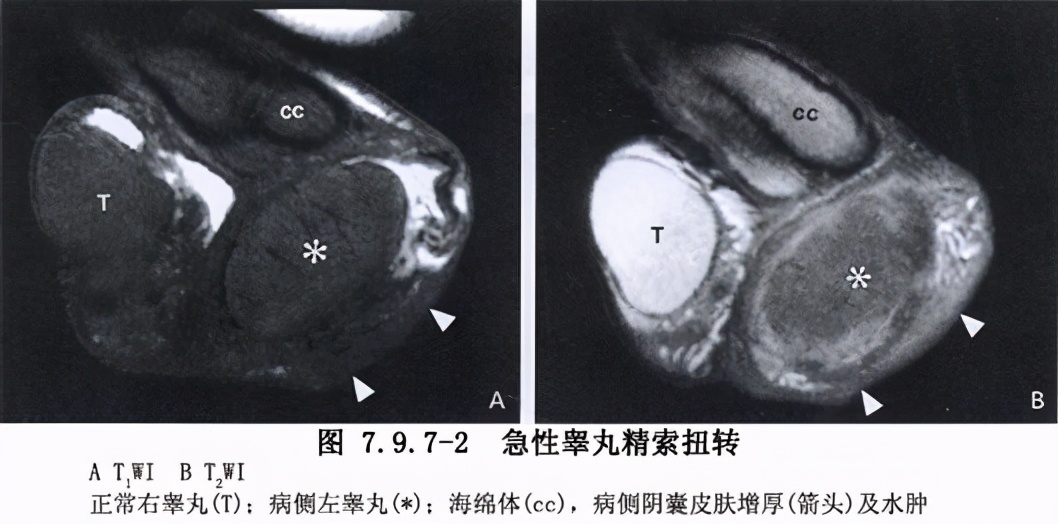

超声检查:少供血型(急性期) 见于不完全扭转(<360°)或早期扭转(<6小时)。*丸睾**大小正常或轻度增大,实质回声均匀,大多数*丸睾**内可探及少量点状血流,动脉血流频谱为低速低阻型。认识此型是挽救*丸睾**的关键,应认真鉴别。

多血供型 见于扭转后松解期。此型*丸睾**形态及回声尚无明显改变,血供则明显增多,动脉血流频谱为高速低阻型,舒张期血流增多,甚至出现反向血流。扭转的血管松解时,缺血的*丸睾**供血突然增多,此现象为缺血组织血流再灌注的“反跳反应”。此型要注意与急性*丸睾**炎症相鉴别。 缺血型 亚急性期(6小时到2周),*丸睾**肿大,回声强弱不均,常有鞘膜积液及血肿形成,*丸睾**内无血流信号;附睾肿大,回声不均。继续发展表现为*丸睾**缩小,实质呈低回声、不均匀,可伴有钙化点。

血供环绕型 在亚急性期,部分病例*丸睾**周围可见一低回声“晕”,彩色多谱勒显示为“彩色晕环”。*丸睾**动脉血流阻断后,提睾肌动脉的分支扩张形成侧支循环,以供应*丸睾**周围组织。